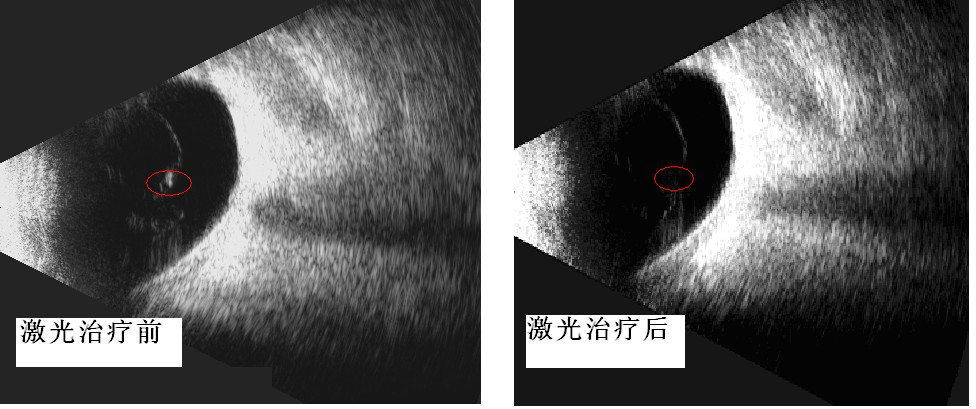

近日我院已为首批飞蚊症患者进行治疗,这些患者倍受飞蚊症折磨,通过2-3次玻璃体激光消融治疗,取得了满意的疗效。从眼部B超检查也显示激光治疗前后玻璃体混浊也有了明显的改善。